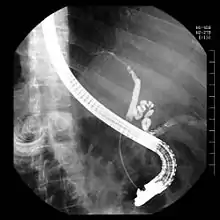

Ендоскоп вводиться через рот в дванадцятипалу кишку, де оглядається і зондується фатеровий сосочок (Papilla vateri), гирло спільної протоки жовчних і підшлункових вивідних шляхів. Контрастна речовина вводиться в жовчні протоки ретроградно, тобто всупереч нормальному напрямку потоку жовчі. Під рентген контролем оцінюють звуження проток, наприклад, внаслідок жовчних каменів (холедохолітіаз), або пухлин .

Перевагою ЕРХП є можливість також одночасно проводити терапію на додаток до діагностики, наприклад, за допомогою інструменту для видалення або роздрібнення каменю, який просувається по робочому каналу ендоскопа. Це видаляє жовчні камені, які вийшли з жовчного міхура в жовчні протоки і вклинилися на вузькому кінці перед фатеровим сосочком. Якщо камінь занадто великий, щоб пройти через розріз або розширений сосочок, заздалегідь виконують механічну, або лазерну літотрипсію.

Терапевтично значущим є причина звуження, наприклад звуження спричиненне пухлинами або запаленням, можна виправити, введенням стента, що відновить потік жовчі та секрету підшлункової залози. Також можливо взяти проби (біопсія), щоб підтвердити підозру на пухлину або запалення за допомогою гістологічного дослідження. Жовчний проток можна також оглянути безпосередньо за допомогою холангіоскопа, який просувається по робочому каналу ендоскопа (Mother-Baby-Technic). Крім того, жовчний проток може бути сонографічно досліджений зондом, (внутрішньопротоковим ультразвуком) (IDUS), який також просувається по робочому каналу.